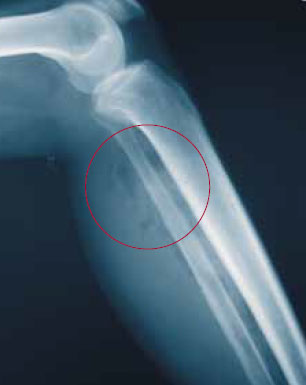

На этой стадии обычно происходит образование газа, который является одной из причин вздутия раненой части тела (рисунок 1). Газ образуется внутри мышечных волокон и между ними, распространяется по фасциальным пространствам и в конце концов уходит под давлением сквозь отверстия в фасции в подкожную клетчатку, быстро распространяясь за пределы инфицированной площади. Под кожей при прощупывании может ощущаться крепитация (похрустывание). Область распространения газа не равна области распространения некроза мышц.

Рисунок 1. Газовая гангрена. На рентгенограмме наблюдается скопление газа между группами мышц